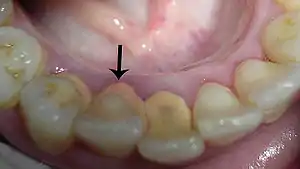

Tartrul se formează cu precădere pe suprafața externă a molarilor superiori, pe suprafața internă a dinților inferiori, dar și în spațiile dintre dinți.

Tartrul supragingival (salivar) este un depozit organomineral de culoare alb-galben, la început de consistență redusă. Imediat după depunere este friabil, moale, grunjos, și se dizlocă cu ușurință. În timp însă consistența și aderența tartrului supragingival cresc, iar culoarea virează spre maroniu-negru – prin impregnare cu pigmenți alimentari, inclusiv din sucuri, sau de hidrocarburi și nicotină la fumători. Localizarea preferențială a tartrului este: grupul frontal inferior și deschiderea canalelor glandelor salivare.

Tartrul subgingival (seric) este de culoare maroniu-negru, de consistență crescută, dens, de cele mai multe ori foarte aderent și mai greu de dizlocat în comparație cu cel supragingival.